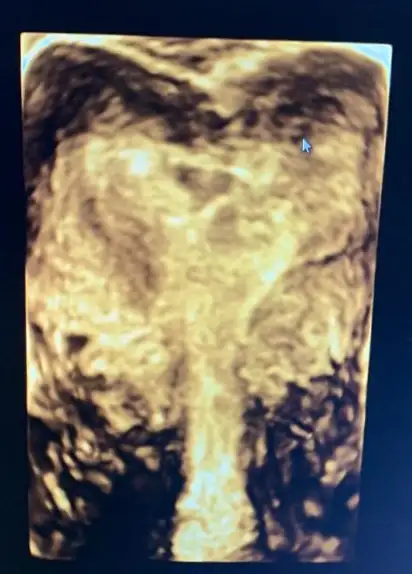

Velhasılı kelam ben de 2 kere düşük yaptım, bu rahim şekliyle gebe kalabilmek oldukça zor iken gebe kalabiliyoruz bu harika. Fakat perdeden dolayı 2 gebeliğimde de 15. Hafta hep düşük yaptım. Histeroskopi oldum, perde alındı. Şuan artık gebeliğimde düşük olmaması gerekiyormuş. Gebe kalabilmeyi bekliyorum.

Sana rahmimin ameliyat öncesi ve sonrasını gönderiyorum fikrin olması açısından